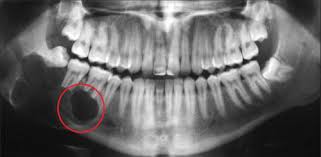

Chụp phim X-quang 3D Conebeam CT để xác định vị trí và kích thước nang.

Nang chân răng (hay còn gọi là nang quanh chóp răng) là túi dịch chứa mủ hoặc mô hoại tử hình thành ở vùng chóp chân răng. Nguyên nhân chủ yếu là do vi khuẩn xâm nhập từ tủy răng viêm, chấn thương hoặc điều trị tủy không triệt để. Nang có thể phát triển âm thầm trong nhiều tháng, thậm chí nhiều năm mà không có triệu chứng rõ rệt.

Nếu không được điều trị, nang có thể phát triển lớn, phá hủy xương hàm, gây tiêu xương ổ răng, thậm chí lan sang các răng kế cận.